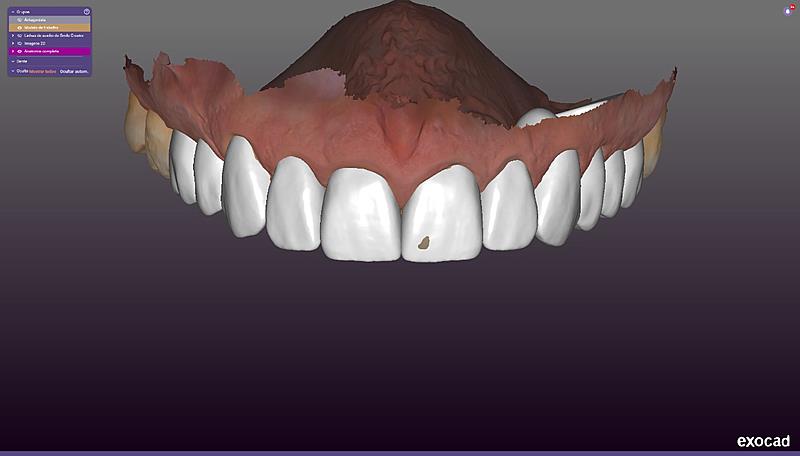

Procedimentos estéticos, cirurgias guiadas e reabilitações orais complexas têm sido realizados com maior precisão por meio de softwares que permitem simulações detalhadas e personalizadas. Um dos profissionais que acompanha de perto esse avanço é o dentista Renês Parizotto, especialista em implantodontia e mestre em prótese dentária, que atua com ferramentas digitais em sua prática clínica.

Entre os recursos utilizados está o escaneamento intraoral, que substitui as tradicionais moldagens com massa. A tecnologia permite captar imagens tridimensionais da boca do paciente com alto grau de fidelidade. Essas imagens alimentam programas que fazem desde o planejamento de cirurgias até a simulação de sorrisos, facilitando a comunicação entre o profissional e o paciente.

Mais recentemente, a inteligência artificial começou a ser aplicada em processos como análise facial automatizada, ajuste digital da mordida e simulações estéticas. Esses recursos oferecem ao dentista mais dados para decisões clínicas e permitem que o paciente visualize o possível resultado antes do início do tratamento.